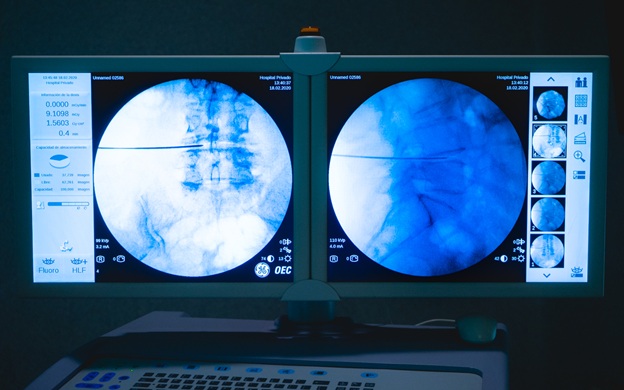

Tecnología e instrumental: su importancia para llevar adelante las MISS

La utilización de las técnicas MISS en un centro médico depende de muchas variables institucionales, como lo son la tecnología y el instrumental disponible. Particularmente Hospital Privado cuenta con aparatos de radioscopia de última generación, sistemas de navegación y técnicos en imágenes, especializados en la patología raquimedular. La razón de la necesidad absoluta de contar con estas herramientas es que la minimización de una ruta de acceso conduce inevitablemente a una visualización más limitada del campo quirúrgico, o a ninguna visualización en absoluto. Por lo tanto, prevalece el uso de imágenes de rayos X para la orientación local, ya que los puntos de referencia anatómicos visuales que alguna vez fueron familiares en condiciones macroquirúrgicas pueden ser indistinguibles u oscurecidos.  En algunos casos intraoperatoriamente, es necesario utilizar sistemas de navegación para verificación del “área objetivo” de manera segura.